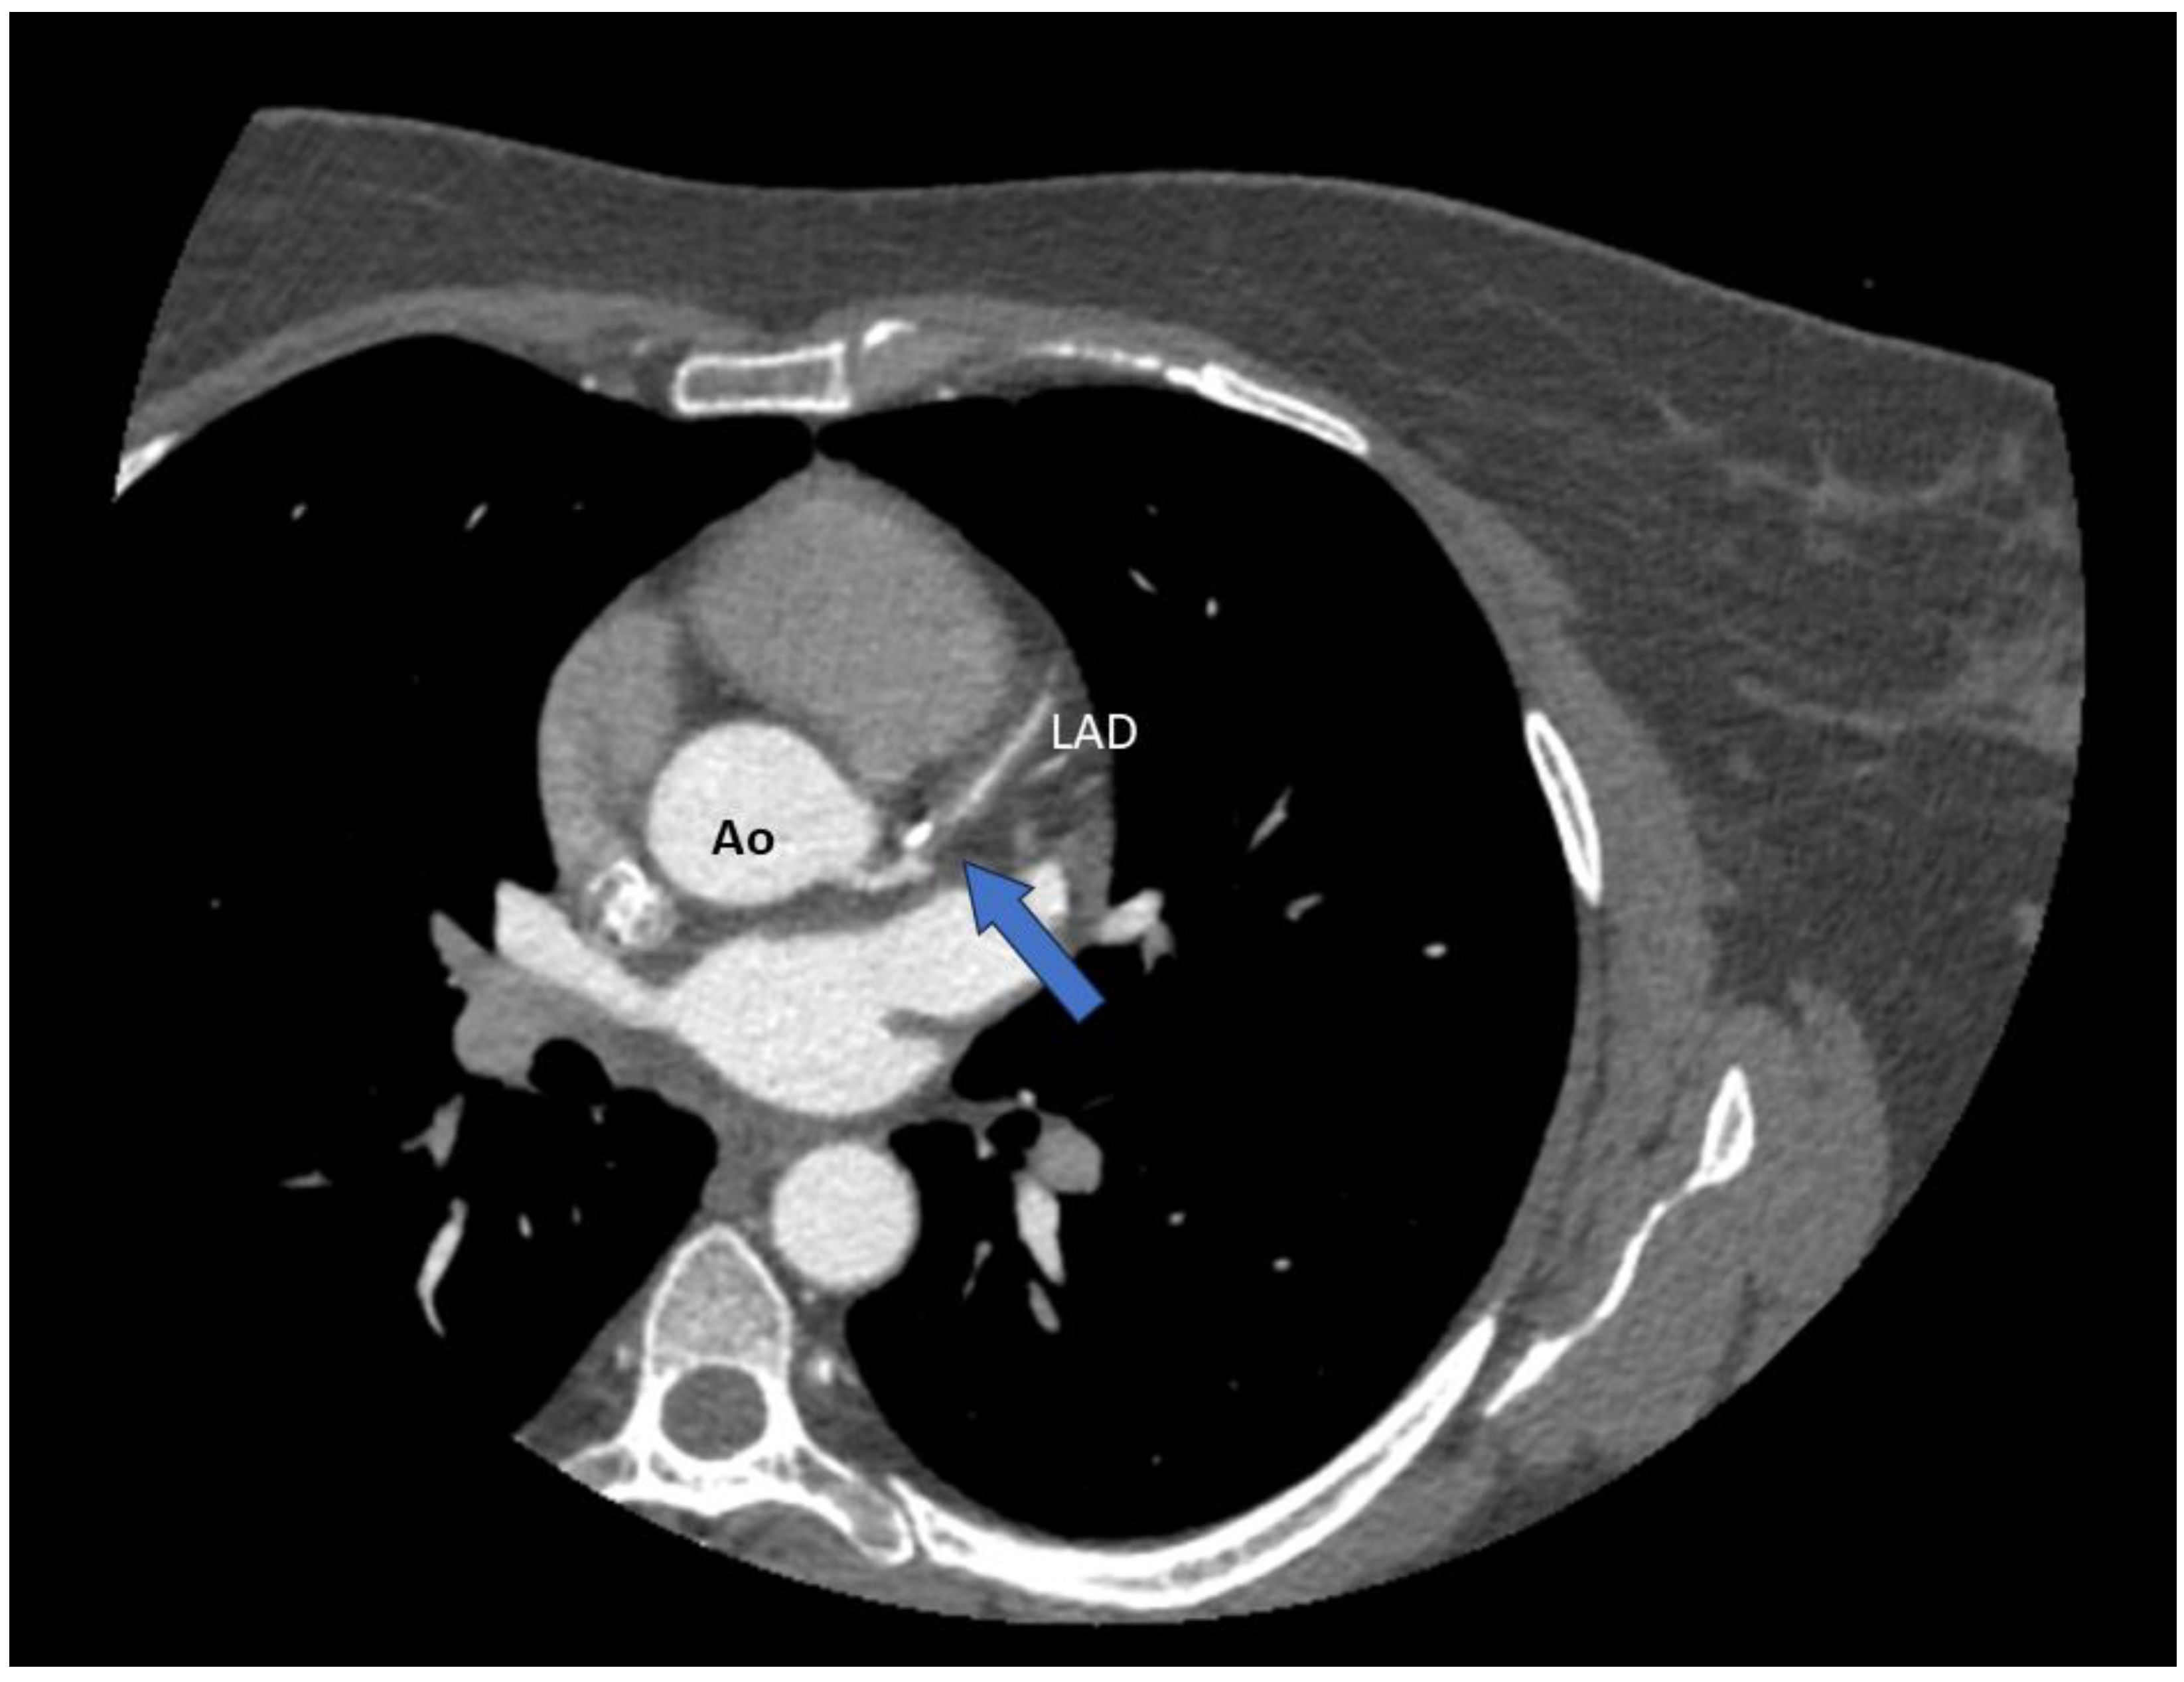

4.2.1. CT Coronary Angiography